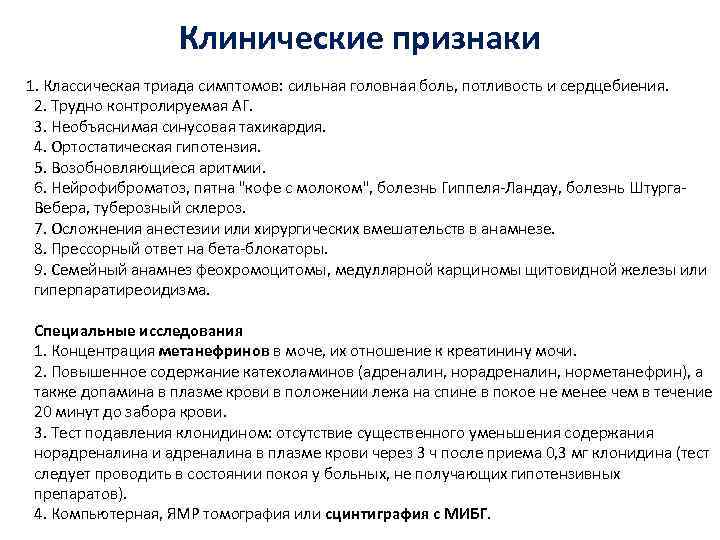

Клинические признаки 1. Классическая триада симптомов: сильная головная боль, потливость и сердцебиения. 2. Трудно контролируемая АГ. 3. Необъяснимая синусовая тахикардия. 4. Ортостатическая гипотензия. 5. Возобновляющиеся аритмии. 6. Нейрофиброматоз, пятна "кофе с молоком", болезнь Гиппеля-Ландау, болезнь Штурга. Вебера, туберозный склероз. 7. Осложнения анестезии или хирургических вмешательств в анамнезе. 8. Прессорный ответ на бета-блокаторы. 9. Семейный анамнез феохромоцитомы, медуллярной карциномы щитовидной железы или гиперпаратиреоидизма. Специальные исследования 1. Концентрация метанефринов в моче, их отношение к креатинину мочи. 2. Повышенное содержание катехоламинов (адреналин, норметанефрин), а также допамина в плазме крови в положении лежа на спине в покое не менее чем в течение 20 минут до забора крови. 3. Тест подавления клонидином: отсутствие существенного уменьшения содержания норадреналина и адреналина в плазме крови через 3 ч после приема 0, 3 мг клонидина (тест следует проводить в состоянии покоя у больных, не получающих гипотензивных препаратов). 4. Компьютерная, ЯМР томография или сцинтиграфия с МИБГ.

Клинические признаки 1. Классическая триада симптомов: сильная головная боль, потливость и сердцебиения. 2. Трудно контролируемая АГ. 3. Необъяснимая синусовая тахикардия. 4. Ортостатическая гипотензия. 5. Возобновляющиеся аритмии. 6. Нейрофиброматоз, пятна "кофе с молоком", болезнь Гиппеля-Ландау, болезнь Штурга. Вебера, туберозный склероз. 7. Осложнения анестезии или хирургических вмешательств в анамнезе. 8. Прессорный ответ на бета-блокаторы. 9. Семейный анамнез феохромоцитомы, медуллярной карциномы щитовидной железы или гиперпаратиреоидизма. Специальные исследования 1. Концентрация метанефринов в моче, их отношение к креатинину мочи. 2. Повышенное содержание катехоламинов (адреналин, норметанефрин), а также допамина в плазме крови в положении лежа на спине в покое не менее чем в течение 20 минут до забора крови. 3. Тест подавления клонидином: отсутствие существенного уменьшения содержания норадреналина и адреналина в плазме крови через 3 ч после приема 0, 3 мг клонидина (тест следует проводить в состоянии покоя у больных, не получающих гипотензивных препаратов). 4. Компьютерная, ЯМР томография или сцинтиграфия с МИБГ.